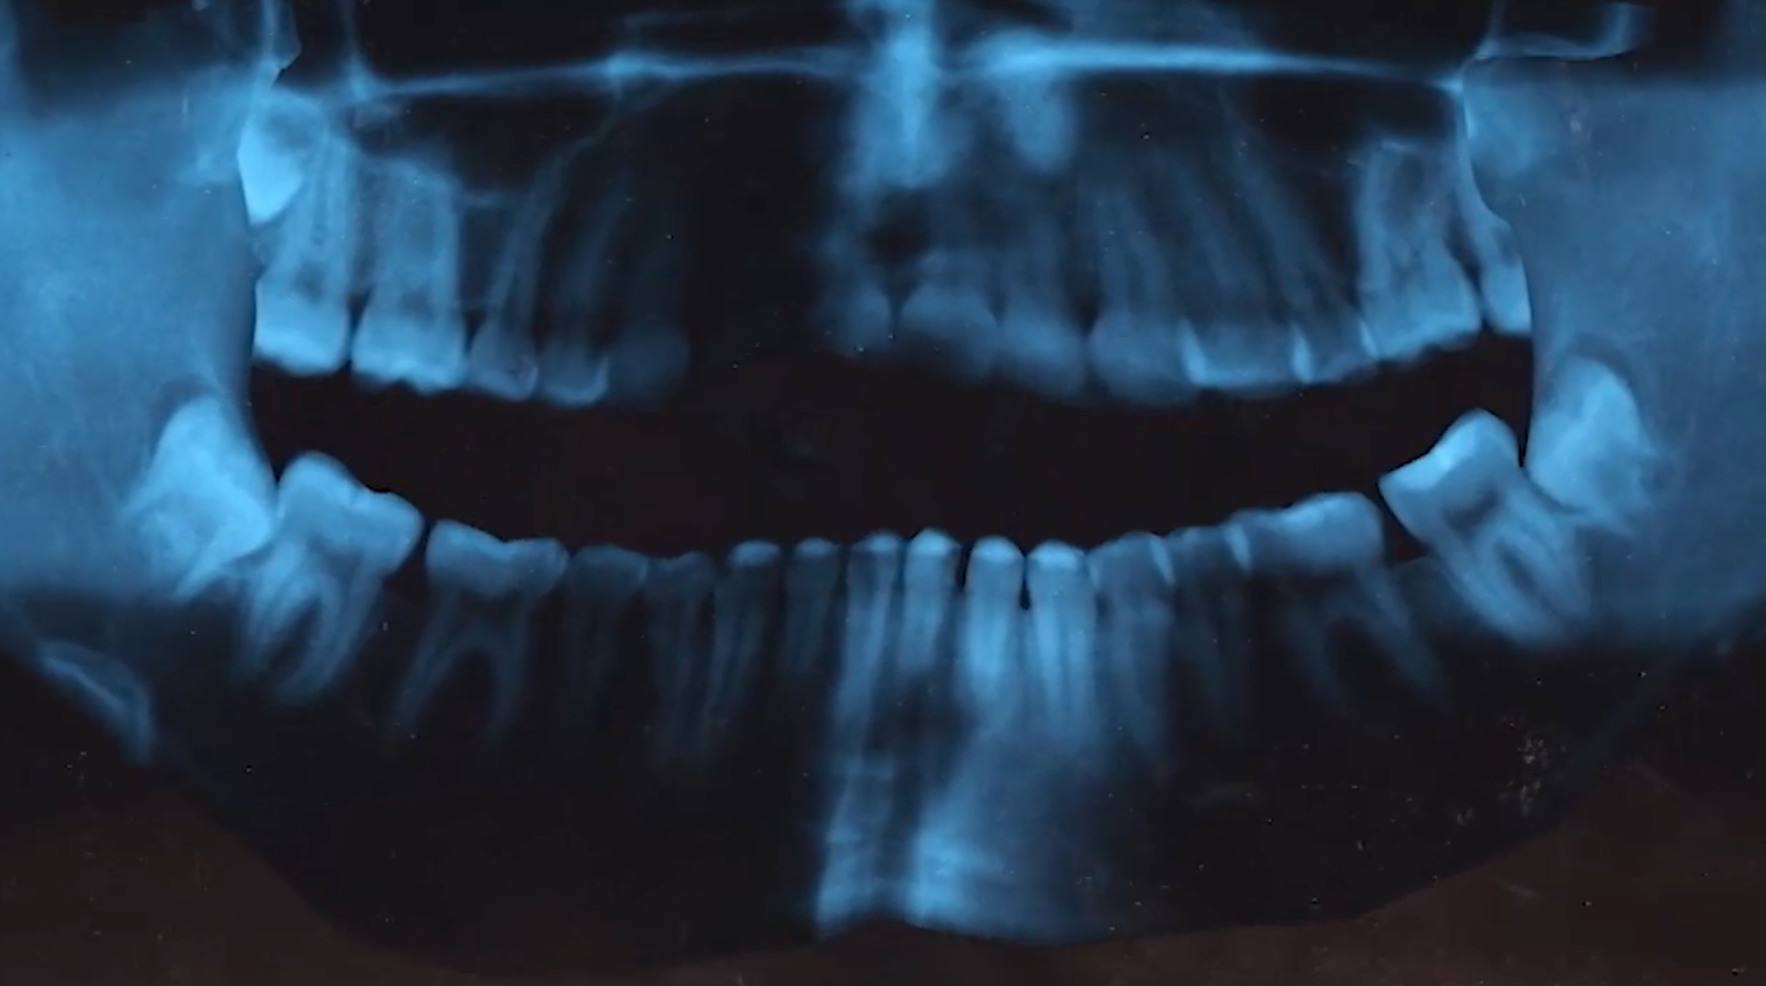

The Smile • 2019

14